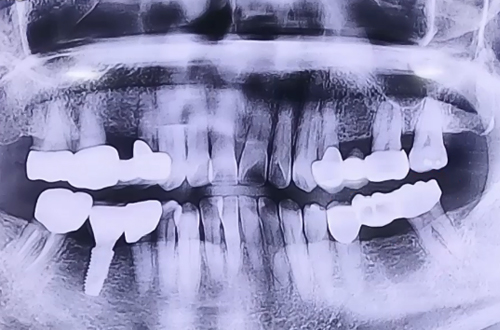

BEFORE

브릿지가 오래되면서 힘을 잃어 오른쪽으로만 식사를 해온 환자분이십니다.

브릿지 제거 후 위아래 남은 양옆의 치아들은 보철로 이를 둘러 씌워주고 임플란트 치료를 마무리해드렸습니다.